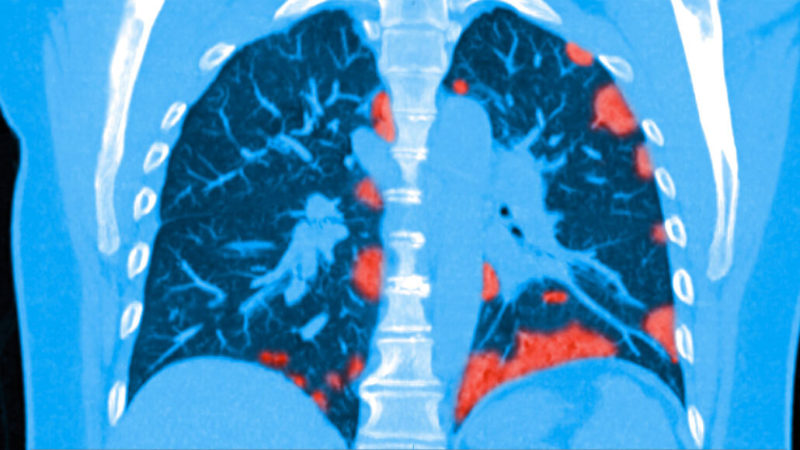

Pneumolog by podle něj měl příchozí „postcovidové“ pacienty komplexně vyšetřit, provést spirometrii a další funkční testy, změřit nasycení kyslíkem jak v klidu, tak po zátěži, vyšetřit plicní difuzi, v případě potřeby nařídit zobrazovací vyšetření plic rentgenem nebo CT. „Už nyní se nám hlásí o vyšetření mnoho zájemců, kteří covid-19 v nedávné době prodělali.